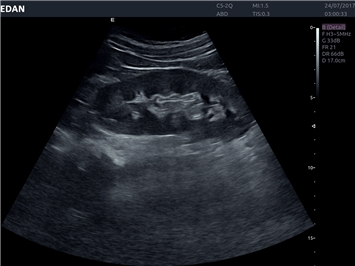

EDAN Acclarix LX4

Расширьте свои представления. Использование усовершенствованной платформой Acclarix система LX4 обеспечивает непревзойденную четкость изображений и интеллектуальный рабочий процесс для всех пользователей, являясь при этом наиболее экономичным решением.

EDAN Acclarix LX4 представляет собой инновационную ультразвуковую систему, построенную на усовершенствованной платформе Acclarix. Сочетание высокого качества визуализации с интеллектуальным рабочим процессом делает эту систему оптимальным выбором для клиник, ценящих эффективность и экономичность.

Области применения:

Система Acclarix LX4 оптимально подходит для:

• Общей визуализации

• Акушерства и гинекологии

• Педиатрии